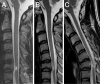

We herein describe a 37-year-old man who developed cervical flexion myelopathy 11 years after suffering a cervical spinal cord injury. Cervical magnetic resonance imaging 11 years after the accident demonstrated atrophy and hyperintense lesions at the C6 and C7 levels in the cervical cord with an abnormal alignment of the vertebrae. In the neck flexion position, an anterior shift of the cervical cord was evident. Our patient's condition suggests that an abnormal alignment of the cervical spine and spinal cord injury due to a traumatic accident could be risk factors in the subsequent development of cervical flexion myelopathy.